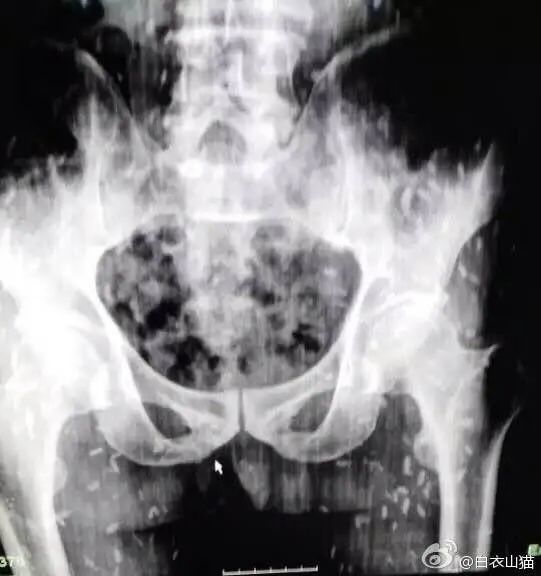

拍了x光片后,也可以看到密集的钙化的死亡的猪肉绦虫囊尾蚴

图片尺寸541x576

寄生虫就是想把机体当巢穴,不然怎么叫寄生虫?

图片尺寸495x587